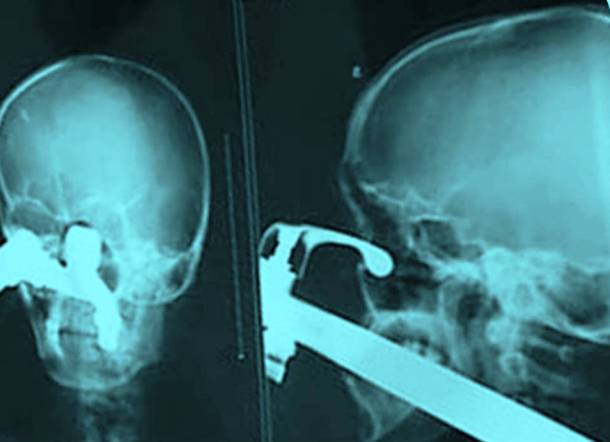

4. A Near Fatal Robbery Defence

This looks fatal - a knife right through the skull right down, reaching the eye socket. This happened when some young men tried to stop a robbery back in 2008. This happened as a result of one of the robbers launching the knife into his head. Thankfully he survived and somehow fully recovered.Advertisement